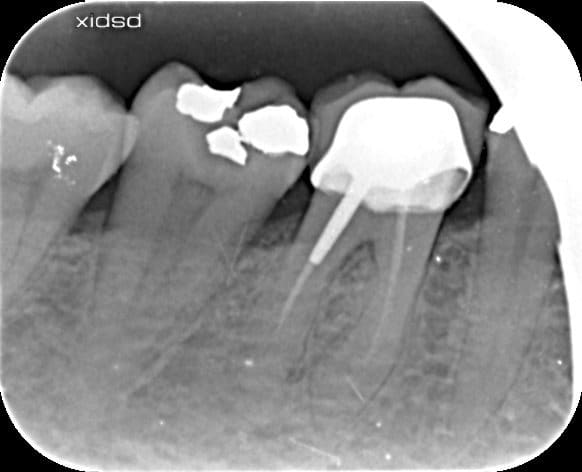

Bonjour j'ai posé cette couronne et fait le traitement endo de 47 il y a 2 mois

depuis le patient a mal a la percussion...

Anatomie atypique, j'avais 2 canaux se rejoignant à l'apex.

Arthrite? léger débordement ccm en m de 47? contrôle point de contact avec 46

3eme canal ??????

j'ai rien vu, rien a signaler lors de l'endo a part l'anatomie atypique de la dent (2 canaux se rejoignant à l'apex)

est ce qu'un cone beam pourrait m'aider à y comprendre quelquechose?